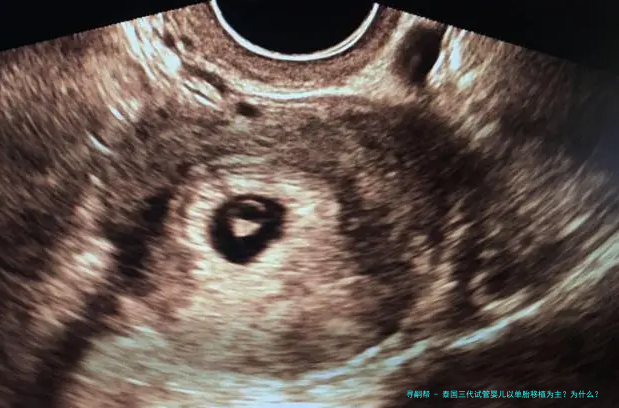

随着多个胎儿条件的放开,女年纪的增长,很多家庭去泰国做试管婴儿,因为要的是多胎,在进行胚胎移植的时候建议移植了一个胚胎。如此,泰国三代试管婴儿以单胞胎移植为主?为什么?下方跟随来一起了解一下吧。

泰国三代试管婴儿以单胎移植为主?为什么?

对于条件理想的患者,括移植2个有可能双胎妊娠的患者,或者因体重、子宫异常不能承受双胎妊娠的这么一部分患者,一般是建议进行单囊胚移植,既能保证她们的妊娠率,也能减低期的各种风险。